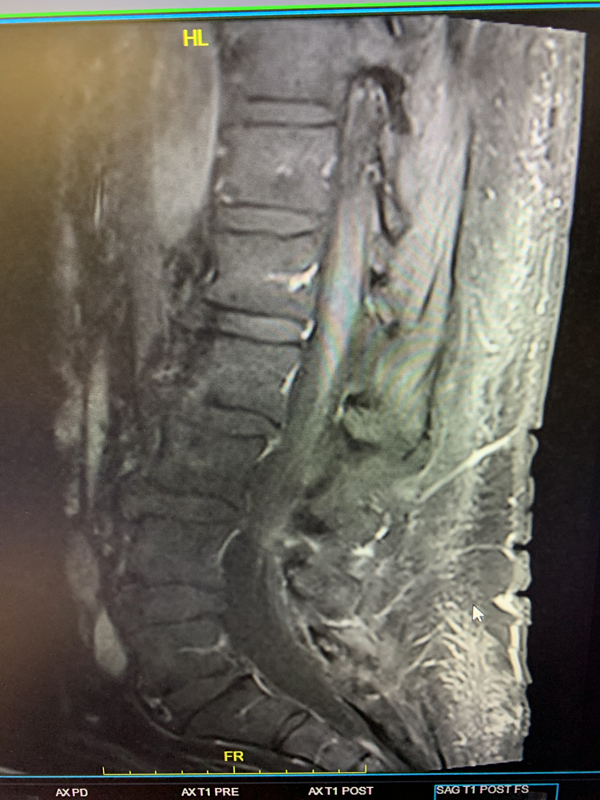

The patient is a 65-year-old woman with a history of hypertension and hypercholesterolemia who was experiencing bilateral lower extremity weakness and numbness for close to one year in addition to some urinary incontinence for the preceding 6 months. The patient ultimately saw a neurologist who ordered an MRI of her lumbar sacral region revealing a bright signal within the lower spinal cord on T2-weighted sequences with enhancement and flow voids seen on the dorsal aspect of the spinal cord suggestive of spinal dural arteriovenous fistula (Figure 1). She was referred for a neurovascular consultation. Physical examination was significant for 4/5 weakness on the right hip and leg muscle groups with decreased pinprick and light touch sensation in both lower extremities in a stocking distribution and decreased vibratory sensation in both toes.

(Figure 1) Pre-treatment MRI image of lumbar sacral region.

Based on the MRI findings and the clinical presentation, a spinal dural fistula was presumptively diagnosed and a spinal angiogram recommended with planned attempt to embolize a fistula if encountered. Spinal angiography confirmed a spinal dural fistula fed from radiculomedullary branches off the left T6 pedicle and draining into a spinal vein (Figure 2B & 2D).

No spinal arteries were identified from this pedicle and after provocative testing with lidocaine and amytol injection confirmed that no arterial input to the spinal cord, the fistula was sealed with one injection of onyx glue (Figure 2C). Post-embolization angiogram confirmed no residual filling of the fistula (Figure 2D).

Pre-Treatment (Figure 2A and 2D), At Treatment (Figure 2B – Onyx Glue Cast), and PostTreatment (Figure 2C)